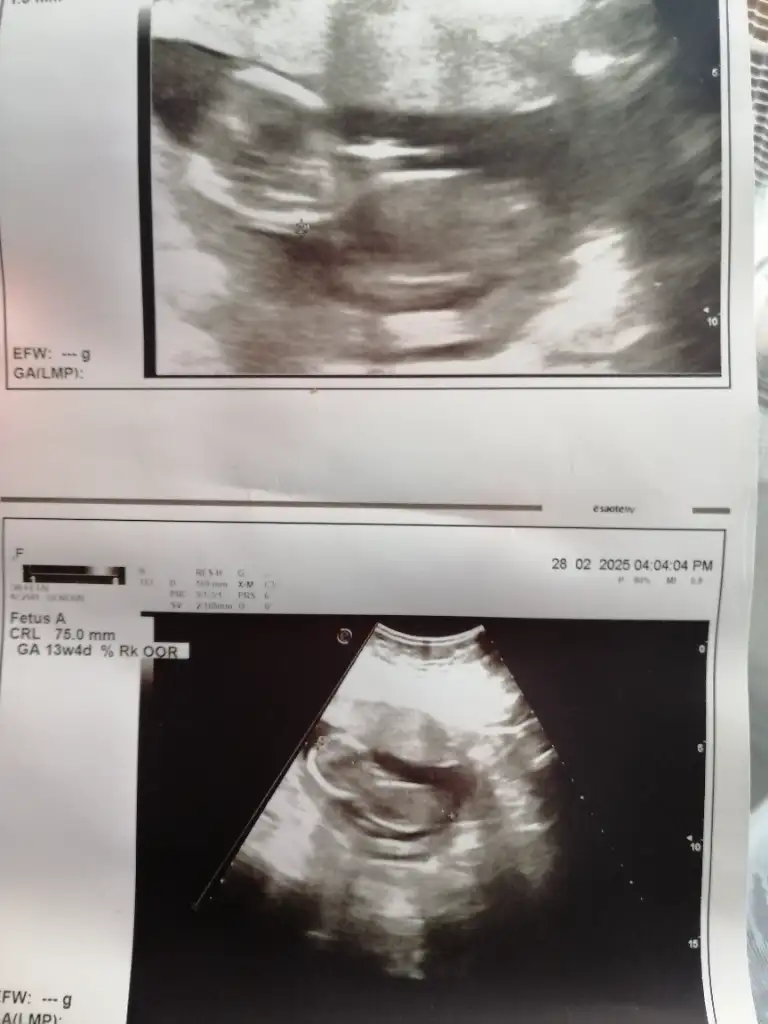

Yaren007 Yaren007 lütfen bana da bşr yorum yapar mısın. Çok yere yazdım dönüş yapan olmadı. Merak ediyorum 🥺

Eklentiler

• IMG_20250307_073925.webp

IMG_20250307_073925.webp

22,9 KB · Görüntüleme: 42